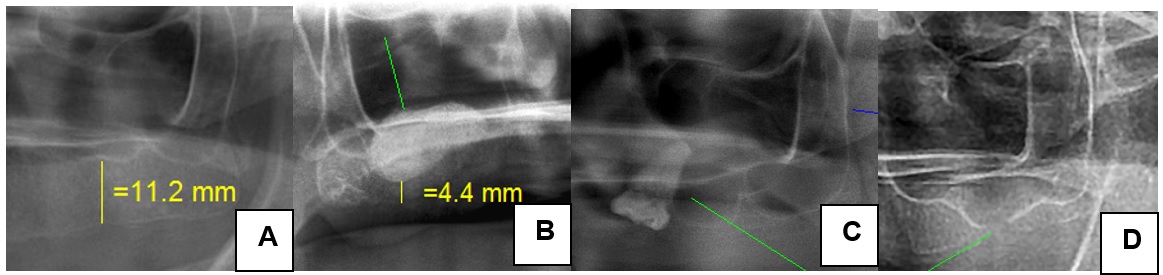

En relación con los hallazgos en el seno maxilar, 92 pacientes (82 %) presentaron neumatización de al menos uno de sus maxilares sin preferencia por la edad, el lado o el sexo. El 1,8 % (2 casos) presentó una comunicación bucosinusal, un resto radicular (0,9 %), un molar (0,9 %) y una maxilectomía (0,9 %) (figura 3).

a) Normal. b) Neumatizado y con presencia de injerto óseo. c) Presencia de molar en el seno maxilar. d) Comunicación bucosinusal

Fuente: elaboración propia.El promedio de las medidas de la altura del reborde alveolar superior fue de 6,5 mm; mientras que en el reborde inferior este fue de 11,1 mm. Los valores para cada uno de los 3 puntos medidos se muestran en la tabla 1. El análisis comparativo no mostró diferencias entre los dos lados (derecho e izquierdo) de la altura de reborde superior e inferior, la altura de los cóndilos y de las ramas mandibulares.